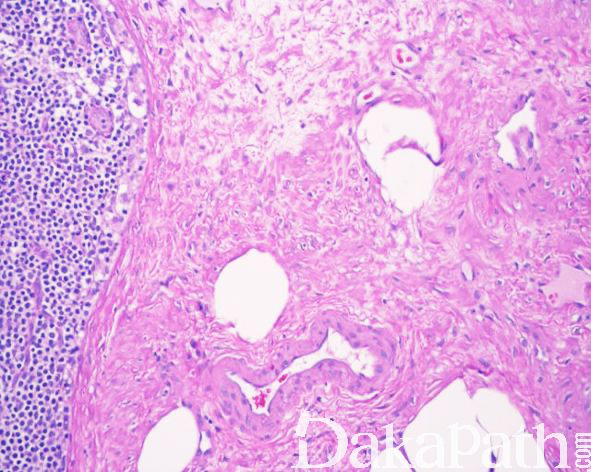

组织学表现为淋巴结实质内的血管肌样增生伴有不同比例的纤维性间质,血管壁通常较厚,管腔大小不等,平滑肌样梭形细胞形态较温和,具有嗜酸性胞浆和顿圆的核,呈疏松或致密的束状排列,无核分裂象和坏死;2/3 的病例内可见散在或广泛呈簇分布的成熟脂肪组织;

较大的病变常弥漫取代淋巴结实质或病变内可见残存的岛状淋巴组织,较小的病变多位数淋巴结中央或门部,周围绕以未受累的淋巴组织;

无淋巴结外扩散,无淋巴管内生长。